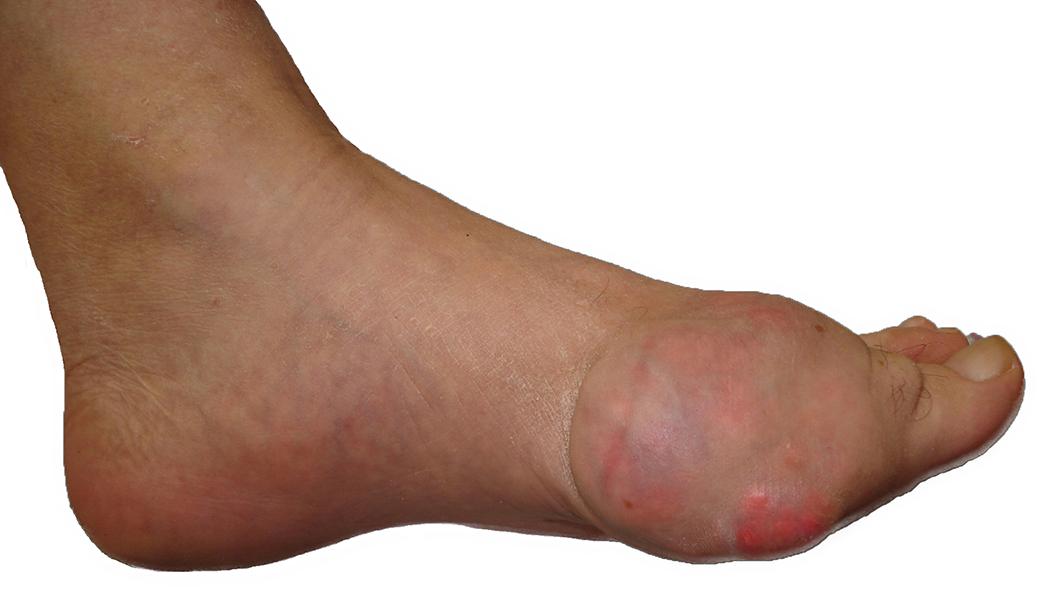

Podagra - Deposição de Ácido Úrico no Hallux

Artrite gotosa é a inflamação aguda das articulações ocasionadas por depósito de cristais de ácido úrico nas paredes internas da cápsula e no líquido articular (líquido sinovial). Essa inflamação causa muita dor, inchaço e vermelhidão ao paciente gotoso.

Normalmente acomete uma única articulação. Um dos locais mais afetados é a articulação do maior dedo do pé (dedão), a chamada podagra. O joelho e o tornozelo também são sítios freqüentes.